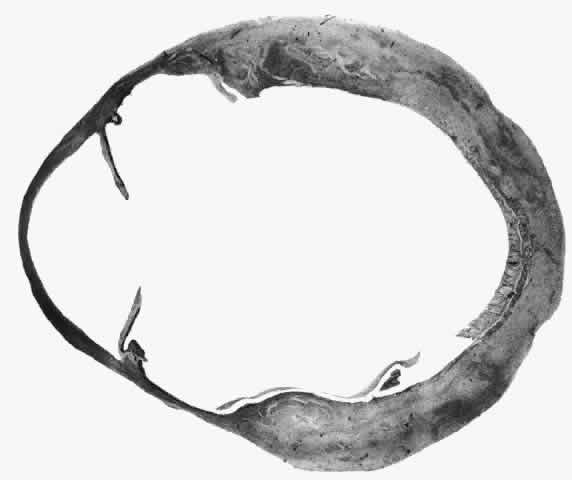

What is clinically represented solely by inflammation and edema is histopathologically a granulomatous lesion of the sclera, the center of which consists largely of plasma cells, lymphocytes, and mast cells (Figs. 21 through 23). Foster and colleagues have identified the cellular subsets and glycoproteins in both necrotizing and non-necrotizing scleritis.22 This shows an active T-cell inflammatory response with a high CD4/CD8 ratio and increased HLA/DR and CD14, indicating a macrophage-induced response that would lead to granuloma formation. Remote from the granuloma, the fibrocytes of the sclera become activated, the proteoglycan adjacent to them becomes altered, and the collagen fibrils of the sclera become unraveled (Figs. 23 and 24). These changes appear to take place prior to the invasion of the stroma by cells of the granuloma.20 The vessels in and around the necrotic area show medial necrosis and perivascular cuffing with lymphocytes, and endothelial swelling with microvascular occlusion. Ninety-six percent of the specimens examined by Foster and associates show a microangiopathy characterized by a neutrophil infiltrate in and around the vessel wall.22–23 This is most obvious at the center of the lesion where there may be occlusion of the vessel, thrombosis, or even aneurysm formation (Fig. 25). From these pathologic investigations, clinical observations, animal experiments, and the results of fluorescein angiography, it would appear that the scleral inflammation is initiated either by trauma (be it accidental or surgical)23–25 or by bacterial or viral infection. If circulating immune complexes are present because of the poor blood flow, they become precipitated in and around the vessel walls in the area of inflammation. In other patients, a persistence of tissue damage will lead to autoimmunization. Damage to the endothelial cells of the microvasculature leads to changes within the vessels detectable on angiography and to catabolic changes in the surrounding tissues. These changes, in turn, allow the granulomatous response that is seen in histopathologic sections, the first detectable change being in the scleral fibrocytes and the proteoglycan and collagen remote from the site of cellular infiltration.